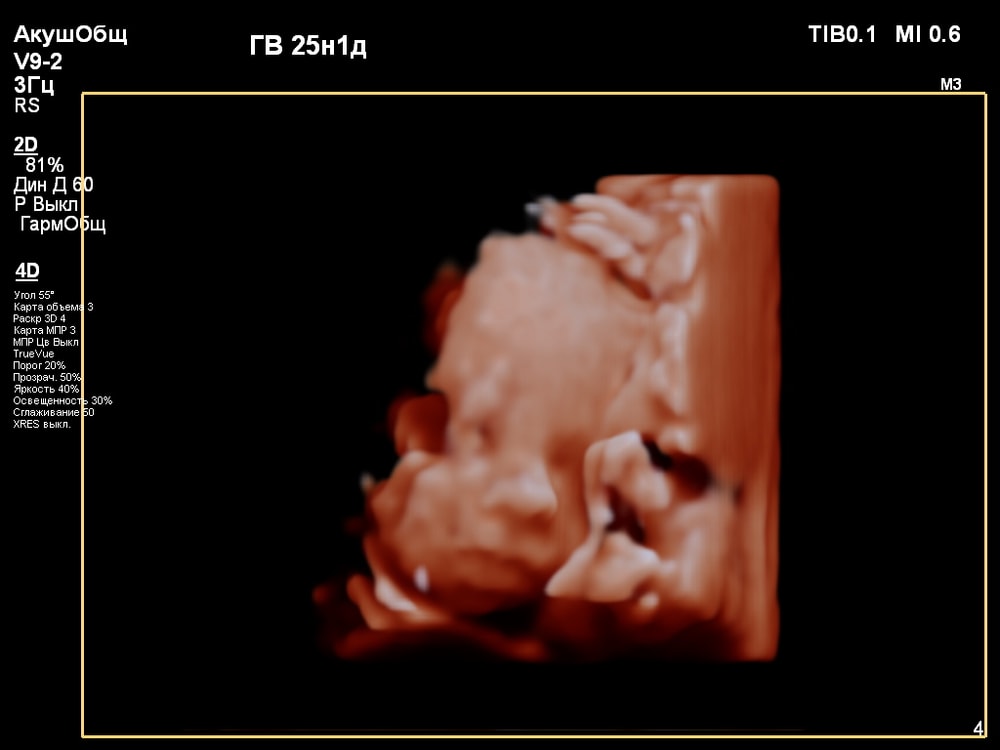

3D/4D УЗИ в 25 недель

УЗИ, КТГ, доплерПервая фотосессия малыша ещё в животике!😍 СНИМКИ С УЗИ👇

Когда переключили на 4D режим было сначала непонятно, что изображено на экране. Но врач всё показывала и обьясняла что на нём: где носик, губки, подбородок, что у личика ручки, малыш что-то жуёт, губками шевелит. Тогда картина начала вырисовываться и всё стало понятно, и в движении тоже)).

За 30 мин удалось увидеть многое (ребёночек не спал)! Он у меня в принципе парень активный, особенно лёжа на спине): на УЗИ, ещё в самом начале, малыш показал указательный палец и почесал им нос 😂, потом пытался большой палец засунуть в рот и пососать. Забавно было, когда он начал зевать и прикрывать ротик ладонью (воспитанный растёт). Ну и конечно, на радость родителям малыш улыбался🥰. Александра Евгеньевна смогла поймать все эти моменты и запечатлеть на снимке). Когда ребёночек закрывался, отворачивался - врач проводила общее 2D исследование, потом возвращалась к 4D.

Иногда получить хорошую картинку сложно. Качество изображения сильно зависит от положения плода, количества околоплодных вод, расположения плаценты, толщины брюшной стенки. Мне в этом плане повезло, плацента была расположена по задней стенке матки, брюшная стенка у меня тоненькая, околоплодные воды в норме, малыш был в движении и можно было разглядеть его профиль.